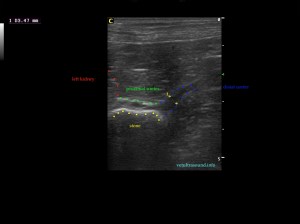

Ευρήματα: Παρουσία λίθου στην πύελο του αριστερού νεφρού ο οποίος καταλάμβανε όλη την κοιλότητά της και εκτεινόταν στο πρώτο τμήμα του ουρητήρα. Ο λίθος προκαλούσε ήπια διάταση του πυελοκαλυκικού συστήματος και του ουρητήρα. Αντίστοιχα στον δεξιό νεφρό βρέθηκε λίθος ο οποίος εντοπιζόταν μόνο στην κοιλότητα της νεφρικής πυέλου. Στην ουροδόχο κύστη βρέθηκε μικρή παρουσία ιζήματος.